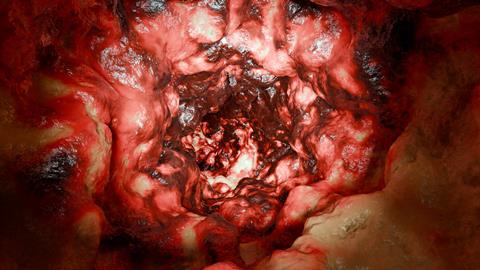

Five distinct CRC prognostic subtypes were identified, which could revolutionise the way CRC is diagnosed and treated.

To molecularly classify colorectal cancer, the researchers developed an integrated analysis approach, combining mutated genes with gene expression levels. This enabled the finding of five distinct CRC prognostic subtypes (CRPSs), each with unique molecular characteristics. This novel classification system could revolutionise the way CRC is diagnosed and treated.